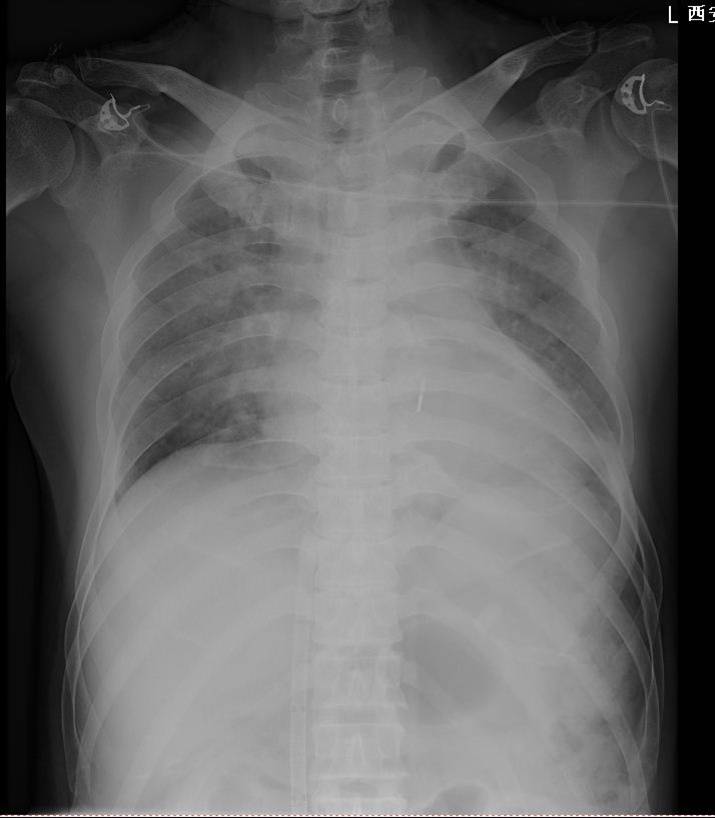

胸片(2016.11.27)

1.两肺大片状渗出影,考虑两肺肺水肿可能;

2.心影大。

胸片(2016-11-29)

◆双肺渗出,考虑肺水肿,心影大,较2016-11-27片相比,心影较前稍增大;

◆心影处可见一线样高密度影,请结合临床。